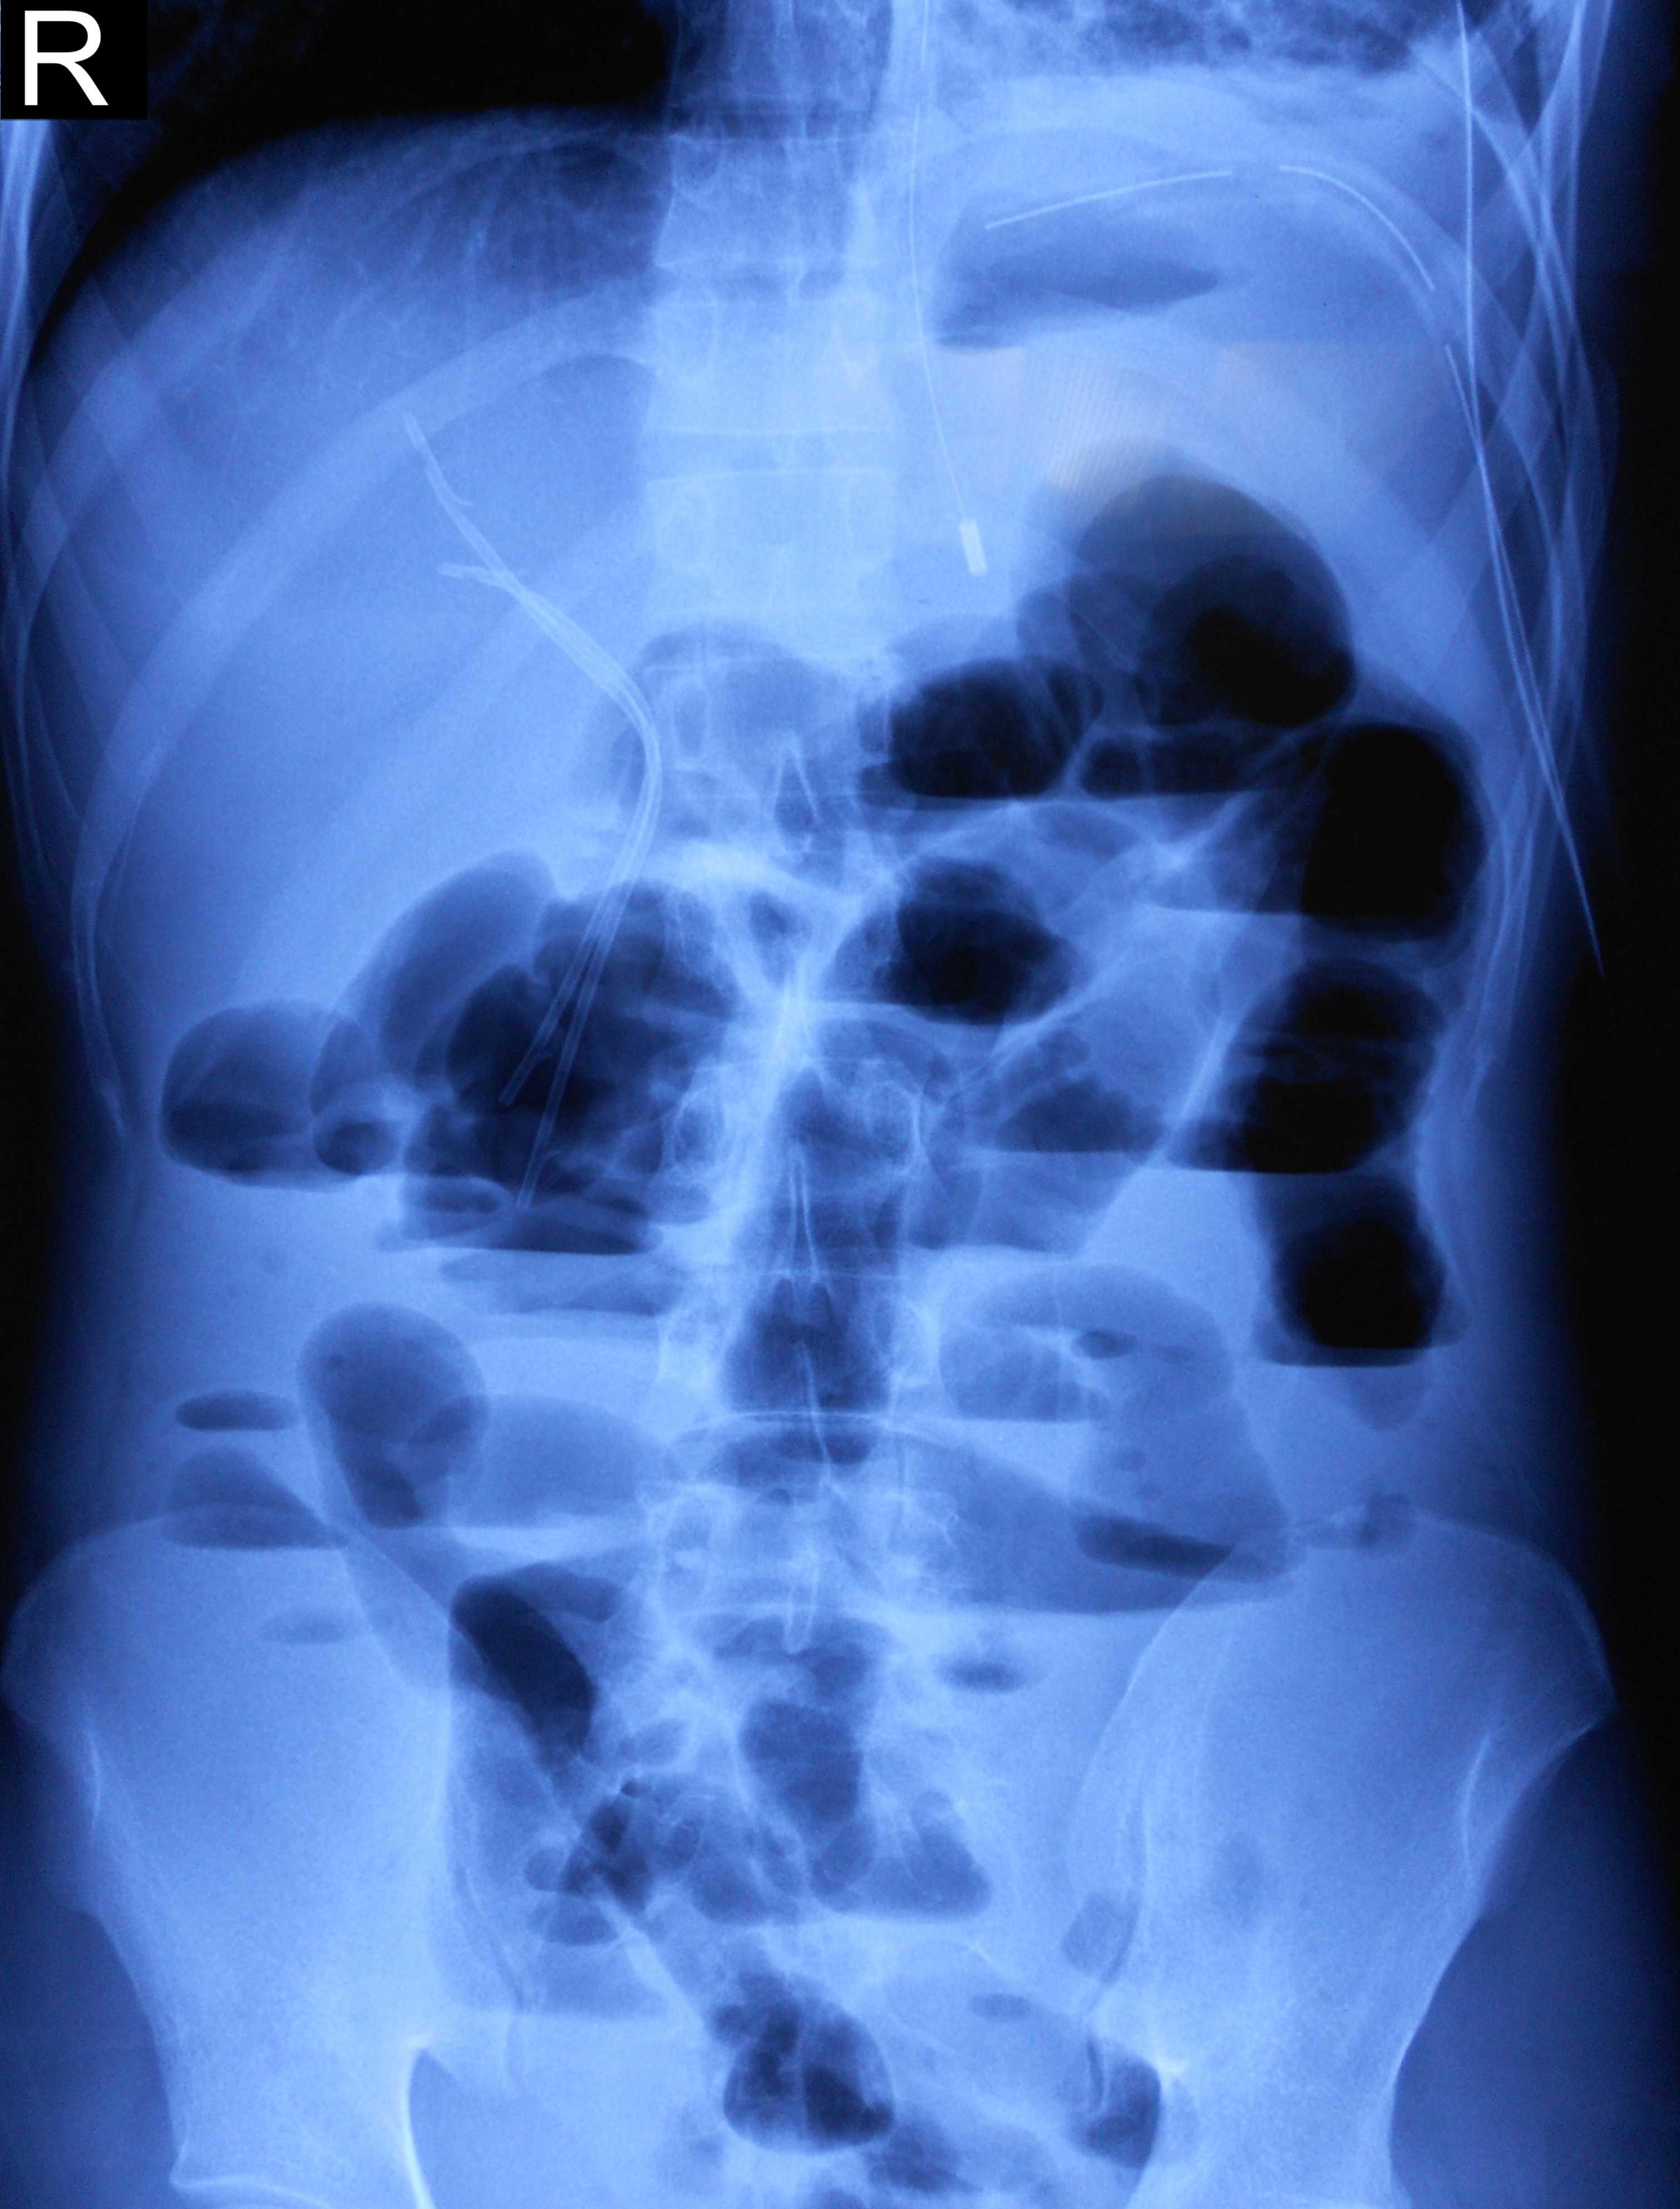

On admission, oral temperature was 100°F, pulse rate was 100/minute, Blood Pressure was 120/80 mmHg, Respiratory rate was 30/min. There was decreased air entry on left lung auscultation and one Intercostal drain (ICD) in situ on left side. Per abdomen examination was insignificant except hepatomegaly. Chest X-ray PA view after aspiration showed hydropneumothorax with clear-cut cyst margins on the left lower region with ICD inside (Figure 1). CECT abdomen and chest revealed two hydatid cysts in the right lobe of the liver (Figures 2 & 3). After all preoperative evaluation, patient was found fit for the surgery. His all hematologic and biochemical parameters were within normal limits. Therefore, it was planned to deal with the lung and liver hydatids at the same sitting under general anesthesia first with liver followed by lung hydatid cyst.

Figure 1 Chest X-ray PA View showing cyst wall with hydropneumothorax and ICDs in situ.